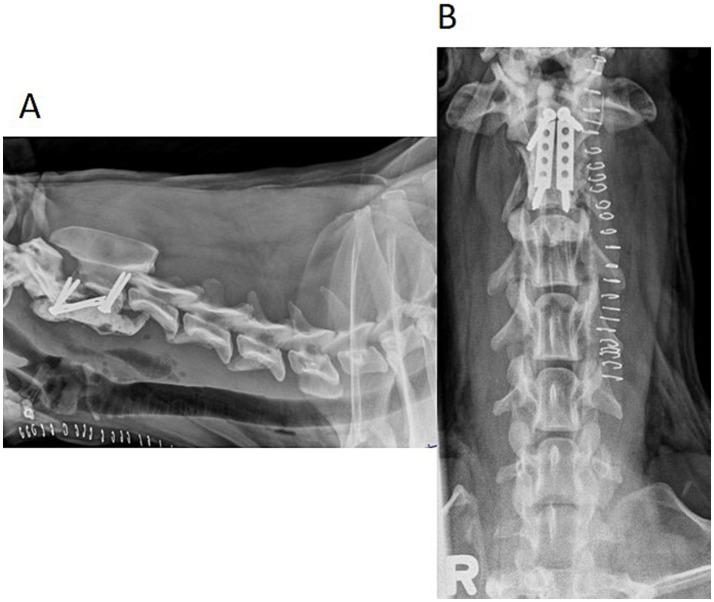

Veterinary cuttable plates (VCPs) were used to maintain reduction and provide reinforcement in screw and polymethylmethacrylate (PMMA) repairs of C2 vertebral fractures in two dogs. A 6-month-old male intact 3.8 kg Shih Tzu and a 4-year-old male intact 30.5 kg Golden Retriever presented after motor vehicle accidents. Computed tomography (CT) scans revealed fractures of the C2 vertebrae in both dogs. Fractures were reduced and stabilized with a combination of cortical screws, VCPs, and PMMA. The novel technique utilized veterinary cuttable plates positioned between screws cranial and caudal to the fracture for distraction and reduction of the fractures and can be incorporated into the acrylic. Post-operative imaging showed adequate fracture reduction and relief of spinal cord compression. Recheck examinations demonstrated a return to normal and near-normal neurologic function in both patients.

在两只犬的C2椎体骨折的螺钉和聚甲基丙烯酸甲酯(PMMA)修复中,使用兽医可切割钢板(VCP)来维持复位并提供加固。一只6个月大、体重3.8千克的未绝育雄性西施犬和一只4岁、体重30.5千克的未绝育雄性金毛寻回犬在机动车事故后就诊。计算机断层扫描(CT)显示两只犬均有C2椎体骨折。通过皮质螺钉、VCP和PMMA的联合使用,骨折得以复位并稳定。这项新技术利用置于骨折部位头侧和尾侧螺钉之间的兽医可切割钢板来牵引和复位骨折,并且可以与丙烯酸材料结合使用。术后影像学检查显示骨折复位良好,脊髓压迫得到缓解。复查显示两名患者的神经功能均恢复到正常或接近正常。